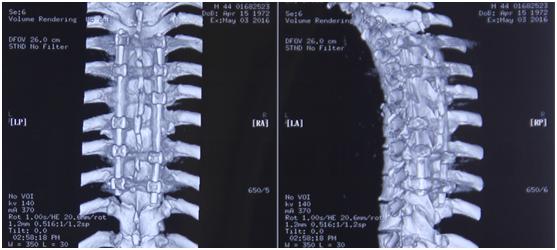

手术前后对比

“我们通过脊间隙制钉把脊柱完全复位了,而且对这个脊髓进行了一期的减压,减除脊髓致压物,很大程度保留脊髓功能。”李维新教授回忆“术中我们看到脊髓搏动是恢复的,而且患者脊髓复位也非常好。”

术后,经过两周的恢复,患者血气胸也逐渐好了,大小便功能恢复、肢体运动也逐渐恢复。